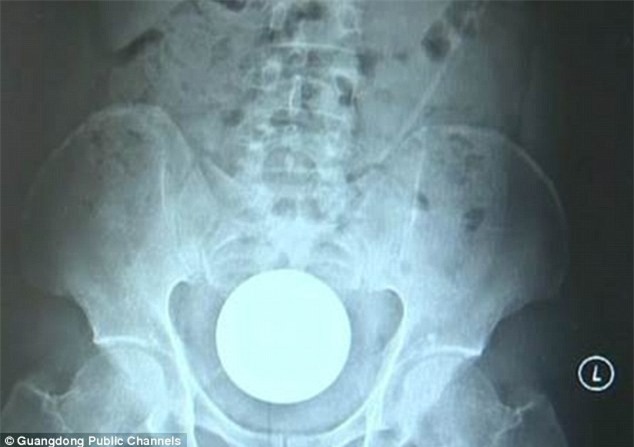

Khi nhập viện, bệnh nhân có triệu chứng đau bụng. Nhiều chẩn đoán đã được đưa ra, nhưng khi chụp X-quang đã phát hiện một vật thể hình tròn có kích thước lớn bên trong. Các bác sĩ đã phải tiến hành phẫu thuật để đẩy dị vật ra ngoài qua đường hậu môn. Sau 1 tiếng, dị vật là quả bóng thủy tinh được lấy ra khỏi cơ thể. Bệnh nhân từ chỗ hốt hoảng dần ổn định tinh thần và hồi phuc sau ca phẫu thuật đơn giản.

Sau 1 tiếng, dị vật là quả bóng thủy tinh được lấy ra khỏi cơ thể người đàn ông.

Bác sĩ đã phải dùng tới kẹp để lấy quả bóng thủy tinh. Theo các bác sĩ, nếu không có sự trợ giúp của các dụng cụ y tế thì bệnh nhân không thể tự lấy được tại nhà. May mắn là bệnh nhân đã nhập viện kịp thời. Nếu chần chờ thêm thời gian có thể khiến cho vùng tiêu hóa bị nhiễm trùng, thủng ruột hoặc nguy hiểm nhất là quả bóng thủy tinh có thể vỡ bên trong. Không ít trường hợp do sợ hãi, lo lắng hoặc ngại ngùng đã để dị vật bên trong cơ thể quá lâu, khi nhập viện thì ruột bị hoại tử, nhiễm trùng nặng việc điều trị là hết sức khó khăn.